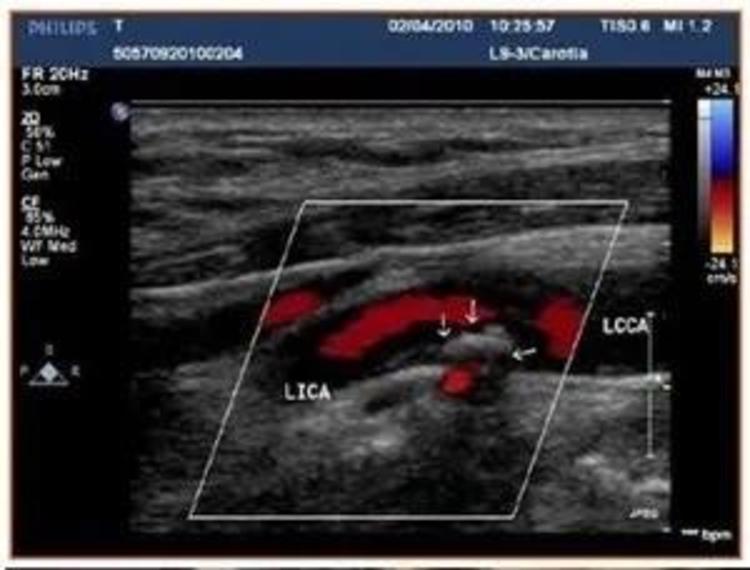

面对重大创伤类的病患,需要采用游离皮瓣移植术技术将人体正常部位的皮瓣切取,移植覆盖在缺损部位上,并将皮瓣内的血管与受区血管进行吻合,以达到营养皮瓣修复缺损的目的。皮瓣游离移植技术中最关键的步骤在于成功分离供区的皮瓣,即皮瓣的切取,此手术要求对于皮瓣供区的主要血管走形、分布、深浅等空间信息都有充分了解,由于人体血管存在一定的解剖变异,因此一般需要在术前通过多普勒B超进行血管位置的判断,并绘制血管的体表投影。但多普勒B超呈现的仍然是二维信息且不够准确,标识血管投影,并解剖出血管需要术者长期的刻苦训练和丰富的临床经验,才能较好完成血管的解剖,受个人主观因素影响较大,成为术中最大的不稳定因素。

昝涛介绍,混合现实技术对于术前准确理解皮瓣的血供特点和血管的空间走形相比于B超以及CT影像来说,具有更加直观、更加符合人的思维习惯的优势。我们可以通过全息数据直接判断非常微细动脉的空间走形,甚至能够判断血管究竟是走形在肌肉还是肌间隙。这对于术前皮瓣设计和规划,同时也对于远程会诊以及病患沟通都具有非常重要的意义。